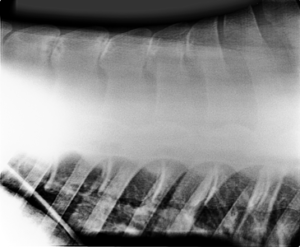

Spierbevangenheid (tying-up, maandagziekte) Aandoeningen & ZiektesBlessures & RevalidatiePaardenvoedingVoorjaarWeidegangZomer